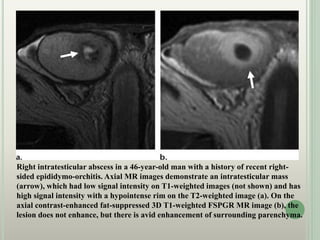

Right intratesticular abscess in a 46-year-old man with a history of recent right-

sided epididymo-orchitis. Axial MR images demonstrate an intratesticular mass

(arrow), which had low signal intensity on T1-weighted images (not shown) and has

high signal intensity with a hypointense rim on the T2-weighted image (a). On the

axial contrast-enhanced fat-suppressed 3D T1-weighted FSPGR MR image (b), the

lesion does not enhance, but there is avid enhancement of surrounding parenchyma.